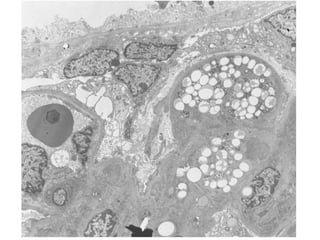

• Trygvason. 1998

– Gen

NPHS1.Cromosom

a19q13.1

– Codifica para la

síntesis de nefrina

de los podocitos

– Se asocia a

síndrome

nefrótico

congénito

– NPHS2 y WT1